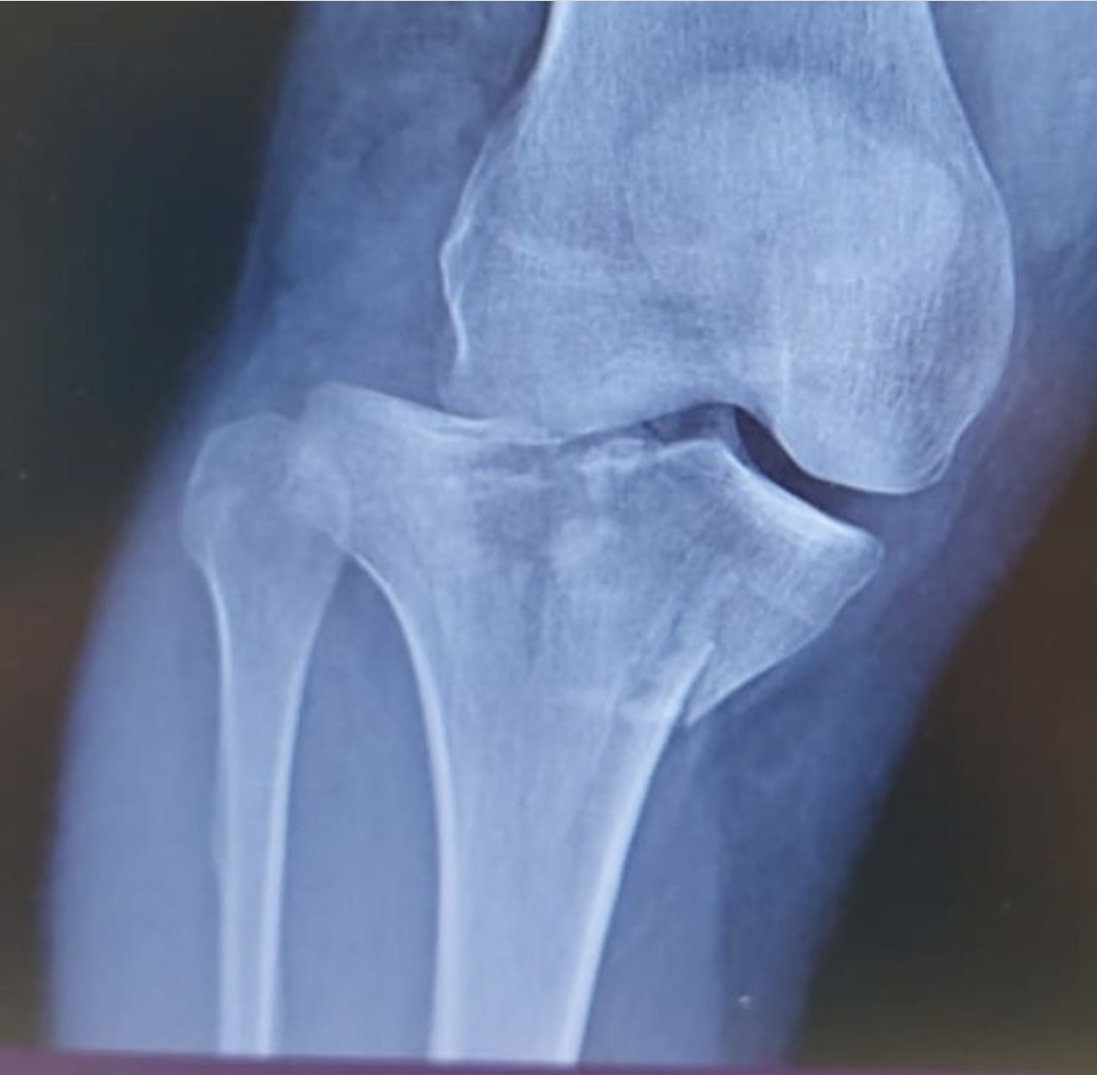

На операционном столе пациент с травмой в результате падения с самоката — многооскольчатый перелом верхнего суставного конца большеберцовой кости с разрывом боковых связок.

«Выполнен остеосинтез пластинами и винтами, восстановлены связки коленного сустава, — рассказывает хирург — травматолог ГКБ 7 Казани Руслан Ильгизарович Закиров. — Самокат в последнее время стал достаточно популярным средством попадания в травматологическое отделение нашей клиники. Большая скорость, маленькие колёса и неровности на дороге, необходимость объезжать пешеходов на тротуаре…. все это пополняет печальную статистику дорожно — транспортных происшествий».